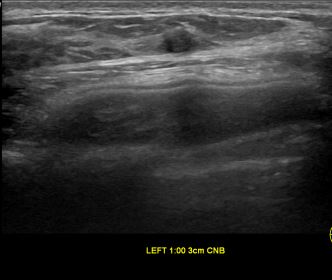

상기환자는 만져지는 멍울있어 검사위해  내원하신 40대 중반

여성분으로 의심스러운 좌측유방혹 조직검사 시행해 유방암으로 진단되었습니다